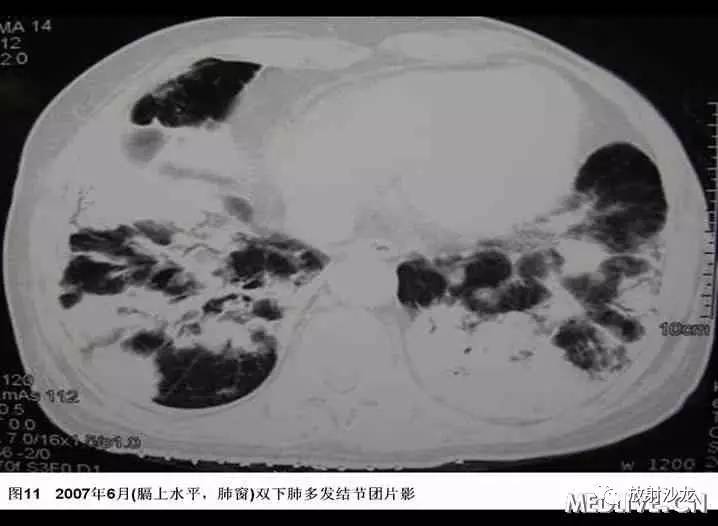

入院后患者最高体温在38℃左右,给予“拜复乐及大扶康”治疗后无显效,复查胸部CT提示肺内病变较2007年3月有加重(见图9-12),遂再次行CT引导下经皮肺穿。穿刺后患者最高体温维持在39℃左右,考虑感染不能完全除外,于2007年6月19日起加用稳可信0.5g Q8h及复达欣1.0g Q8h,6月21日加用口服大扶康200mg Qd,发热未见改善。结合两次肺穿及外院VATS的标本,病理科诊断“肺Castleman病(多中心型)(见图13)” 免疫组化:CD3(+)、CD20(+),AE1/AE3(+),CD21(+)”。6月21日转入血液科化疗,并于6月22日予CHOP方案化疗(CTX 600mg d1, 400mg d4, 西艾克4mg d1, 艾达生80mg d4, 强的松80mg d1-5)。化疗后未再发热,咳嗽、咳痰症状缓解,6月27日复查CXR示右下肺团块影较1月前吸收予以一疗程CHOP化疗后,患者体温正常,复查胸片提示右下肺阴影较前有明显吸收。后又间断予以CHOP方案化疗3程,2008年2月初,因受凉后发热,出现渐加重的气短,家属及患者放弃进一步诊疗,于2008年2月下旬去世。